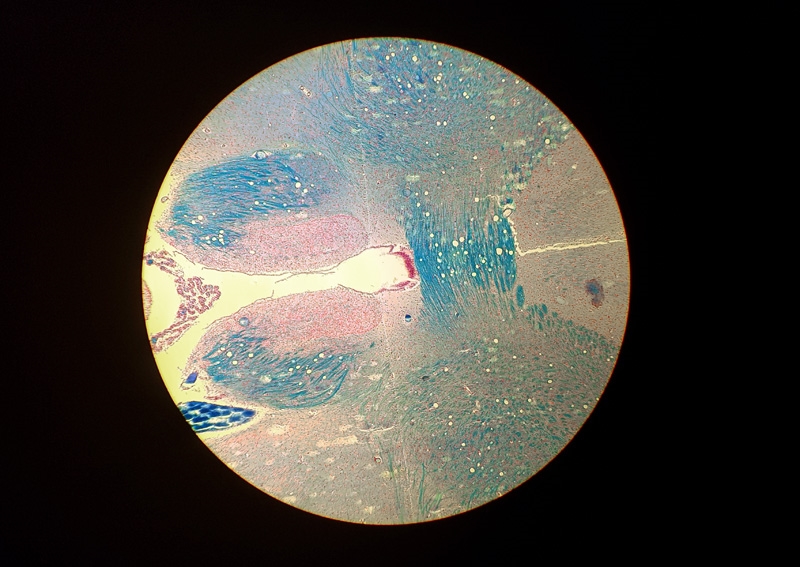

Hallo Ronald, auf dem ersten Bild sieht man ein Foto, dass mit dem Samsung S7 durch ein Periplan GF 10x aufgenommen wurde. Von einem digitalen Zoom habe ich abgesehen. Schade, dass Smartphones keinen 2x optischen Zoom haben. Damit wäre viel gewonnen.

Das zweite Foto enstand mit einer Pentax K-3 über einem Zeiss Kpl W 10x Okular am LEitz Ortholux II. Die Kombination ergibt nur in der Mitte ein gutes Foto; zum Rand hin bricht es ein. Aber es zeigt mehr vom Bild als mein Periplan GF 12,5x MF Okular vor der Kamera, welches das Bild stärker beschneidet.

Ich hätte nichts dagegen, mit der DSLR den vollen oder leicht angeschnittenen Kreis aufzunehmen, weil die Auflösung der Sensoren groß genug für die nachträgliche Auswahl eines Ausschnittes ist.

Tom

Foto mit dem Smartphone Samsung S7

Foto der DSLR und dem Zeiss Kpl W 10x. Das Okular passt nicht zu den Leitz Objektiven, Das sieht man vor allem in Richtung Bildecken an den starken Farbsäumen. Mit meinem Leitz PEriplan GF 12,5 MF ist das Bild besser, aber der Ausschnitt noch kleiner.

Vergleich beider Bilder. Die DSLR nimmt einen zu kleinen Bereich auf.